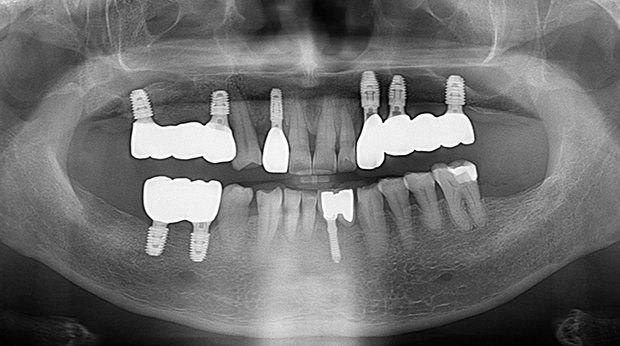

임플란트와 사랑니 발치는 외과적 시술로 잇몸을 절개하는 외과적 시술은

짧으면 짧을 수록 시술 후 붓기와 통증이 최소화됩니다.

치과의사 경력 14년차 구강외과 전문의가 빠르고 안전하게, 아프지 않게 수술해 드립니다.

치과경력 14년차 구강외과 전문의

연세대학교 치과대학 구강외과 임상 조교수